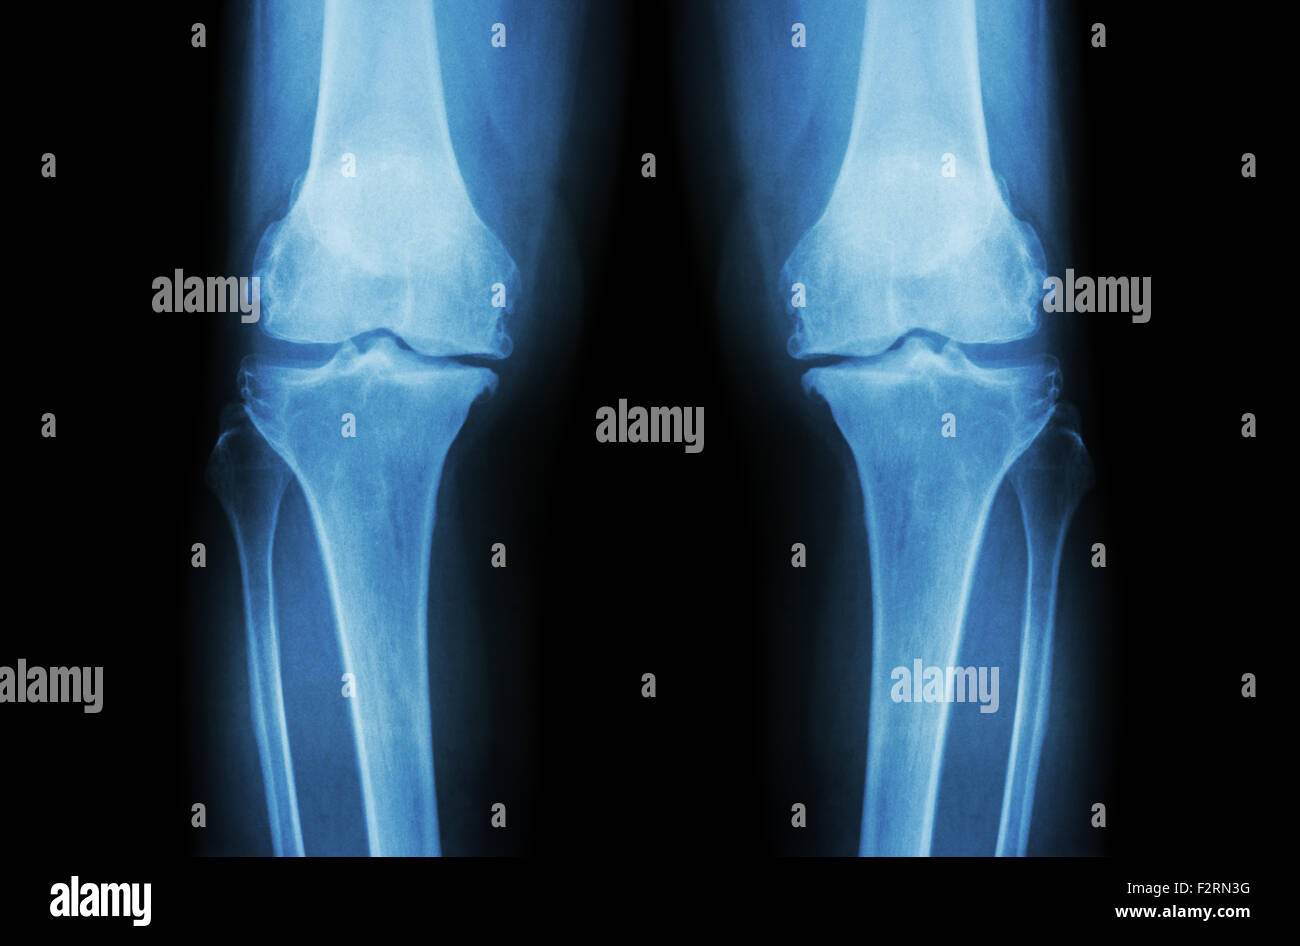

L'ARTHROSE DU GENOU Arthrose du genou ( ). Film x-ray deux genou ( vue avant ) show spatial commun étroit ( perte de cartilage ) , osteophy Banque D'Imageshttps://www.alamyimages.fr/image-license-details/?v=1https://www.alamyimages.fr/photo-image-l-arthrose-du-genou-arthrose-du-genou-film-x-ray-deux-genou-vue-avant-show-spatial-commun-etroit-perte-de-cartilage-osteophy-87802628.html

L'ARTHROSE DU GENOU Arthrose du genou ( ). Film x-ray deux genou ( vue avant ) show spatial commun étroit ( perte de cartilage ) , osteophy Banque D'Imageshttps://www.alamyimages.fr/image-license-details/?v=1https://www.alamyimages.fr/photo-image-l-arthrose-du-genou-arthrose-du-genou-film-x-ray-deux-genou-vue-avant-show-spatial-commun-etroit-perte-de-cartilage-osteophy-87802628.htmlRFF2RN44–L'ARTHROSE DU GENOU Arthrose du genou ( ). Film x-ray deux genou ( vue avant ) show spatial commun étroit ( perte de cartilage ) , osteophy

L'ARTHROSE DU GENOU Arthrose du genou ( ). Film x-ray deux genou ( vue avant ) show spatial commun étroit ( perte de cartilage ) , osteophy Banque D'Imageshttps://www.alamyimages.fr/image-license-details/?v=1https://www.alamyimages.fr/photo-image-l-arthrose-du-genou-arthrose-du-genou-film-x-ray-deux-genou-vue-avant-show-spatial-commun-etroit-perte-de-cartilage-osteophy-87802655.html

L'ARTHROSE DU GENOU Arthrose du genou ( ). Film x-ray deux genou ( vue avant ) show spatial commun étroit ( perte de cartilage ) , osteophy Banque D'Imageshttps://www.alamyimages.fr/image-license-details/?v=1https://www.alamyimages.fr/photo-image-l-arthrose-du-genou-arthrose-du-genou-film-x-ray-deux-genou-vue-avant-show-spatial-commun-etroit-perte-de-cartilage-osteophy-87802655.htmlRFF2RN53–L'ARTHROSE DU GENOU Arthrose du genou ( ). Film x-ray deux genou ( vue avant ) show spatial commun étroit ( perte de cartilage ) , osteophy

L'ARTHROSE DU GENOU Arthrose du genou ( ). Film x-ray deux genou ( vue avant ) show spatial commun étroit ( perte de cartilage ) , osteophy Banque D'Imageshttps://www.alamyimages.fr/image-license-details/?v=1https://www.alamyimages.fr/photo-image-l-arthrose-du-genou-arthrose-du-genou-film-x-ray-deux-genou-vue-avant-show-spatial-commun-etroit-perte-de-cartilage-osteophy-87802612.html

L'ARTHROSE DU GENOU Arthrose du genou ( ). Film x-ray deux genou ( vue avant ) show spatial commun étroit ( perte de cartilage ) , osteophy Banque D'Imageshttps://www.alamyimages.fr/image-license-details/?v=1https://www.alamyimages.fr/photo-image-l-arthrose-du-genou-arthrose-du-genou-film-x-ray-deux-genou-vue-avant-show-spatial-commun-etroit-perte-de-cartilage-osteophy-87802612.htmlRFF2RN3G–L'ARTHROSE DU GENOU Arthrose du genou ( ). Film x-ray deux genou ( vue avant ) show spatial commun étroit ( perte de cartilage ) , osteophy

L'ARTHROSE DU GENOU Arthrose du genou ( ). Film x-ray deux genou ( vue avant ) show spatial commun étroit ( perte de cartilage ) , osteophy Banque D'Imageshttps://www.alamyimages.fr/image-license-details/?v=1https://www.alamyimages.fr/photo-image-l-arthrose-du-genou-arthrose-du-genou-film-x-ray-deux-genou-vue-avant-show-spatial-commun-etroit-perte-de-cartilage-osteophy-87802643.html

L'ARTHROSE DU GENOU Arthrose du genou ( ). Film x-ray deux genou ( vue avant ) show spatial commun étroit ( perte de cartilage ) , osteophy Banque D'Imageshttps://www.alamyimages.fr/image-license-details/?v=1https://www.alamyimages.fr/photo-image-l-arthrose-du-genou-arthrose-du-genou-film-x-ray-deux-genou-vue-avant-show-spatial-commun-etroit-perte-de-cartilage-osteophy-87802643.htmlRFF2RN4K–L'ARTHROSE DU GENOU Arthrose du genou ( ). Film x-ray deux genou ( vue avant ) show spatial commun étroit ( perte de cartilage ) , osteophy